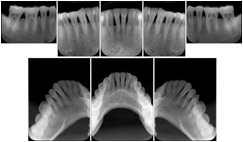

2. A patient requests cosmetic surgery to enhance their facial appearance. The case requires consultation between an orthodontist in New York and an oral surgeon in California. The cephalometric series of 2D projections constructed from the volumetric CT data that is used for the discussion is arranged by a Structured Display for transfer between the two practitioners.

Cephalometric Series Structured Display

Figure OO-2. Cephalometric Series Structured Display